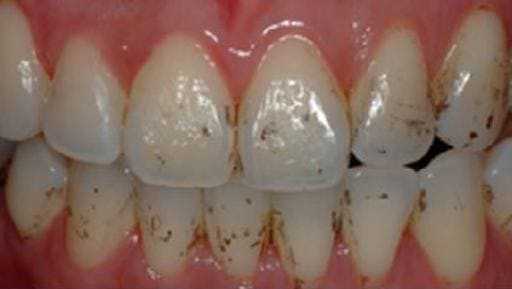

На странице представлено портфолио стоматологий Москвы с работами до и после профессиональной чистки зубов. В нашем портфолио собраны разные клинические случаи: от удаления незначительного налета до снятия массивного поддесневого камня. Здесь вы можете увидеть, как возвращается естественный цвет и внешний вид зубов после процедуры. Изучите результаты до и после чистки зубов, чтобы увидеть реальный эффект и выбрать клинику в Москве, где профессиональная гигиена поможет вернуть зубам здоровый вид.

Чистка зубов Air-flow